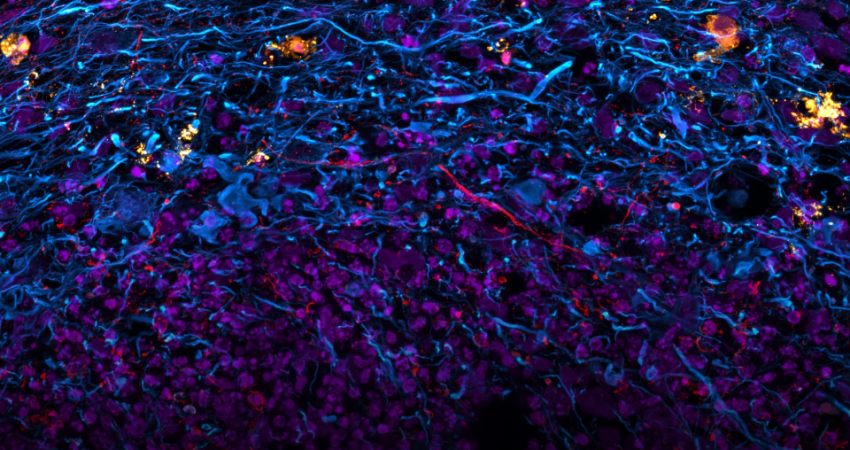

Kjo shkrepje është shumë thellë nw lëkurë. Ju po shikoni një imazh të grupimeve të melanomës metastatike.

Një pamje cerebrale e një trurit të rritur në mënyrë sintetike. Kjo mini kopje e organit është më e vogël se një thjerrëz dhe përfaqëson në mënyrë të përkryer lidhjet e ndërlikuara të trurit të njeriut në zhvillim.